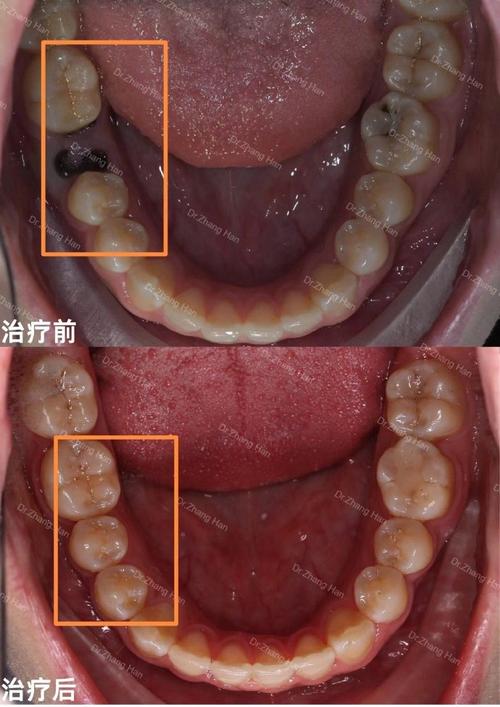

- 口腔健康问题:部分萌出的智齿易嵌塞食物,引发智齿冠周炎(表现为牙龈红肿、疼痛、张口受限),甚至导致邻牙龋坏。